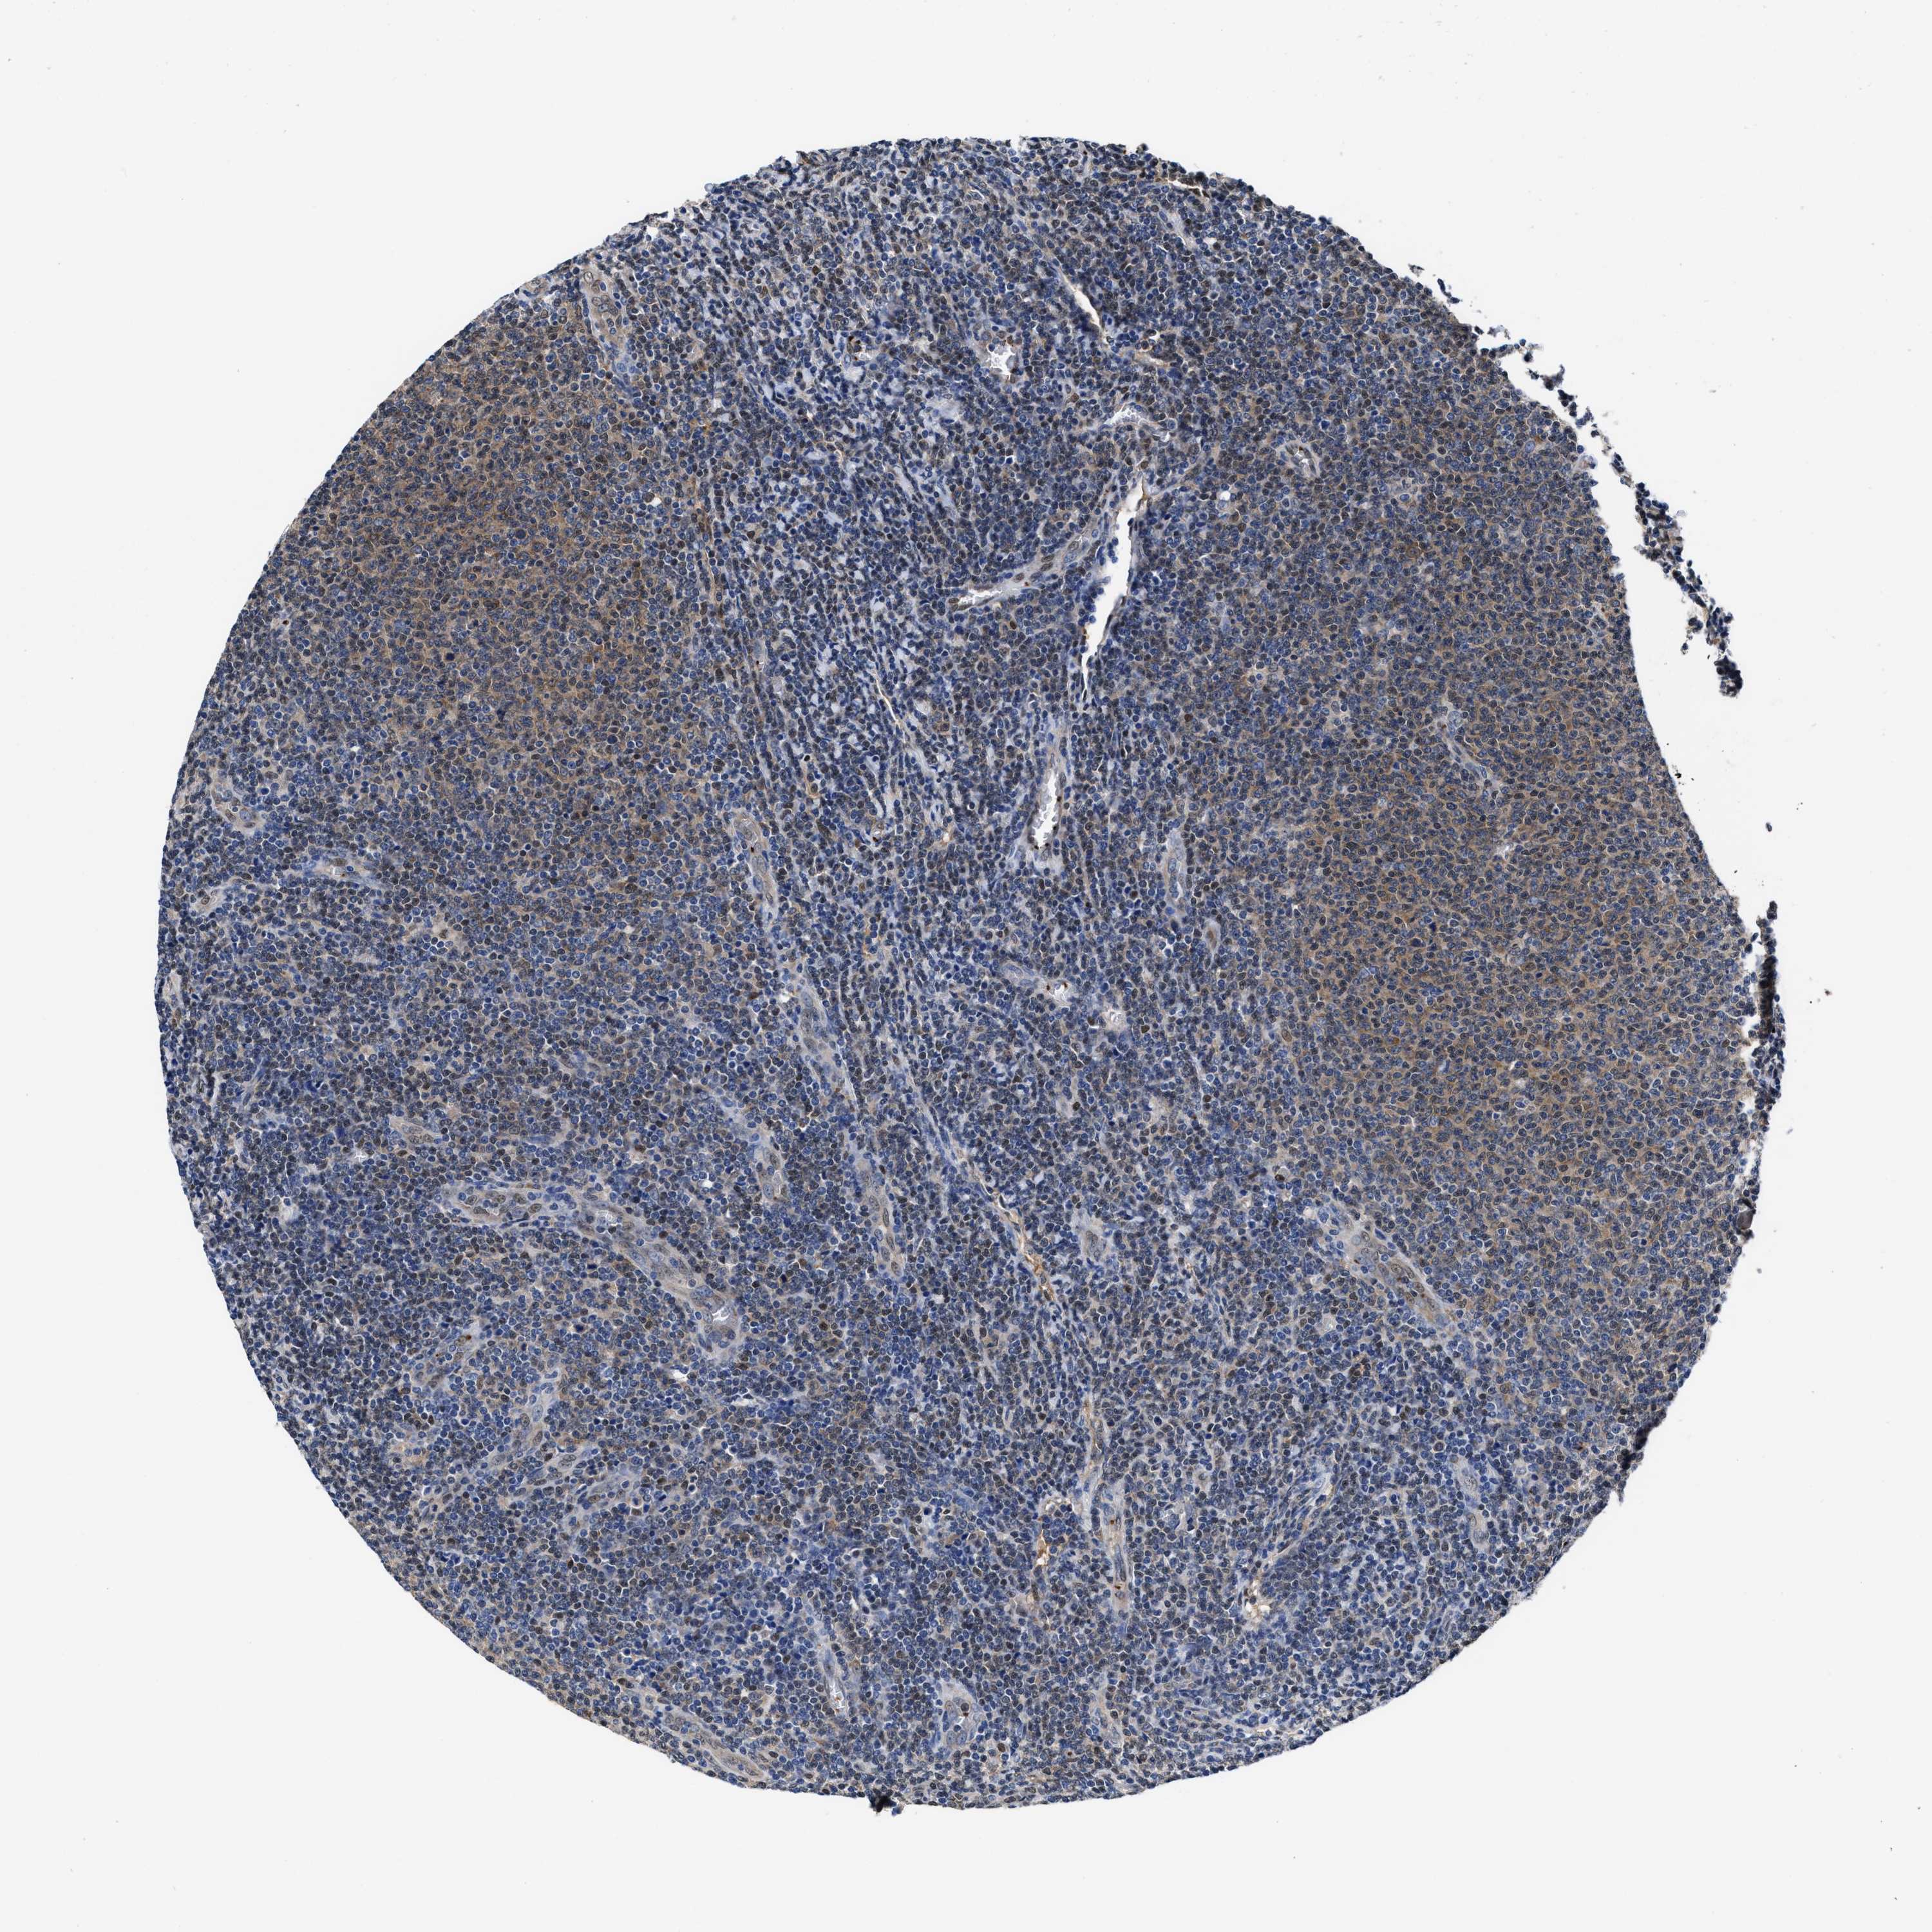

CANCER LYMPHOMA Show tissue menu

LYMPHOMA - Protein expressioni

A mouse-over function shows sample information and annotation data. Click on an image to view it in a full screen mode. Samples can be filtered based on level of antibody staining by selecting one or several of the following categories: high, medium, low and not detected. The assay and annotation is described here.

Antibody stainingi

Antibody staining in the annotated cell types in the current human tissue is reported as not detected, low, medium, or high, based on conventional immunohistochemistry profiling in selected tissues. This score is based on the combination of the staining intensity and fraction of stained cells.

Each image is clickable and will lead to virtual microscopy that enables deeper exploration of all samples and also displays staining intensity scores, fraction scores and subcellular localization as well as patient and tissue information for each sample.